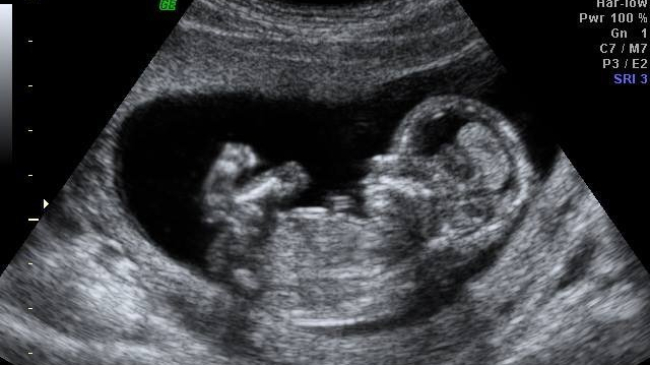

И без того очень неоднозначная и острая тема стала ещё более спорной в связи с новым исследованием. Специалисты выяснили, что уже на 13-ой неделе беременности человеческий эмбрион достаточно развит, чтобы ощущать боль.

Стюарт Дербишир, ведущий автор научной работы, говорит, что женщины, которые решились на аборт, должны осознавать, что эмбрион способен чувствовать боль уже на тринадцатой неделе беременности. Дербишир отмечает, что новые данные заставляют относиться к искусственному прерыванию беременности как к "моральному безрассудству".

Американский исследователь Джон Бокманн заявил, что способность эмбриона чувствовать боль на тринадцатой неделе вызывает некоторые вопросы, однако на восемнадцатой неделе зародыш уже точно может ощущать болевые ощущения, так как к этому сроку уже в достаточной степени формируются его мозг и нервная система, а также связи между ними.

А вот Клэр Мерфи из Британской консультативной службы по беременности придерживается старых взглядов и не желает верить в новые данные — эксперт говорит, что плод не может чувствовать боль до двадцать четвертой недели. Соответственно, беременность можно прерывать без лишних рассуждений о моральной стороне вопроса — добавляет Мерфи.